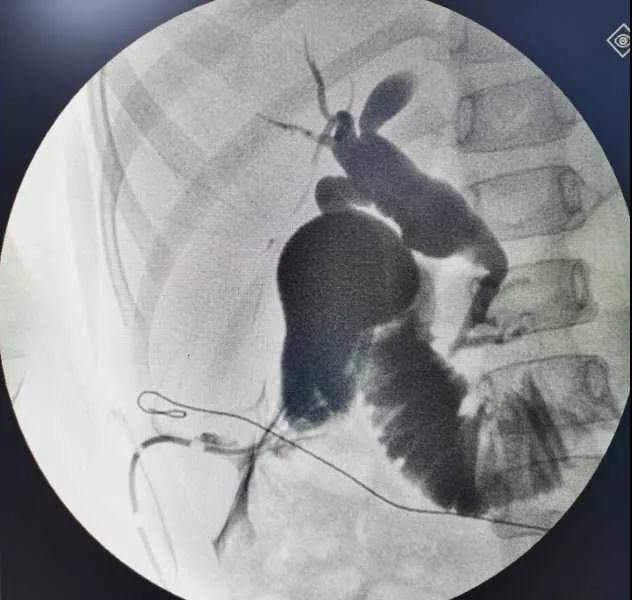

5月7日,西安國際醫(yī)學(xué)中心醫(yī)院小兒外科郭正團(tuán)教授團(tuán)隊(duì)成功為1名膽總管囊腫患兒進(jìn)行了腹腔鏡膽管造影 腹腔鏡膽總管囊腫切除 腹腔鏡肝管空腸吻合術(shù)。目前,患兒恢復(fù)良好,已正常進(jìn)食。

入院后,謝崇醫(yī)生積極為患兒完善術(shù)前準(zhǔn)備,MRCP(核磁共振膽道水成像)顯示該患兒為膽總管囊腫Ic型,有明顯的胰膽合流異常。面對復(fù)雜的病情,小兒外科郭正團(tuán)主任立即組織團(tuán)隊(duì)進(jìn)行術(shù)前討論,制定了完善的手術(shù)方案及應(yīng)急措施。

5月7日,一切準(zhǔn)備就緒,郭正團(tuán)主任主刀,帶領(lǐng)小兒外科團(tuán)隊(duì)進(jìn)行腹腔鏡膽管造影 腹腔鏡膽總管囊腫切除 腹腔鏡肝管空腸吻合術(shù)。術(shù)中,患兒膽總管與周圍肝動脈及門靜脈粘連嚴(yán)重,給手術(shù)增加了難度。郭正團(tuán)主任沉著冷靜,操作嫻熟,完整剝離了膽總管囊腫及遠(yuǎn)端胰腺段膽管,肝總管與空腸完成了Roux-en-Y吻合,手術(shù)進(jìn)行順利。術(shù)后第2天,玲玲就可以下床活動;第6天,已正常飲食。